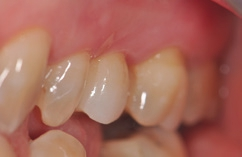

Für den Reentry wurde für das Einbringen des Gingivaformers eine minimale krestale Inzision angelegt (Abb. 13). Nach Abheilung der Weichgewebe (Abb. 14) konnte 2 Wochen später mit Reposition des Abformpfostens geschlossen abgeformt (Abb. 15) und das Meistermodel erstellt werden Da es sich um ein 2-teiliges Implantatsystem handelt und die Abutments ebenfalls aus hochfester ATZ-Keramik bestehen, lassen sich diese – falls nötig – entweder in der Praxis oder im Dentallabor durch Beschleifen individualisieren (Abb. 16). Für NobelPearl stehen sowohl gerade als auch 15° abgewinkelte Abutments mit 1 mm und 3 mm Gingivahöhe zu Verfügung. Im CAD/CAMVerfahren wurde eine monolithische Zirkonkrone aus Zolid FX (Amman Girrbach) mit okklusalem Zugang zum Schraubenkanal gefertigt (Dentallabor Studio für Zahntechnik, Dirk Tartsch).

Die mit dem Abutment verklebten Restaurationen konnten nun entnommen, Zementüberschüsse (Abb. 22) sicher entfernt und die Übergänge von Krone zu Abutment poliert werden. Für die definitive Eingliederung ist der für die Abutmentschraube vorgegebene Anzugstorque von 25 Ncm einzuhalten. Nach erneutem Auffüllen der Schraubenkanäle wiederum mit Teflonband wurden die Zugangskavitäten in ebenfalls üblicher Weise mit Komposit verschlossen. Das Ergebnis sind im vorliegenden Fall 2 metall- und zementfreie, verschraubte und reversible Einzelzahnrestaurationen (Abb. 23). Bei dem routinemäßig durchgeführten Follow-up 6 Monate nach Eingliederung zeigte sich eine an beiden Implantatpositionen reizlose Weichgewebssituation (Abb. 24a und b) und in den radiologischen Kontrollaufnahmen stabile periimplantäre Knochenverhältnisse (Abb. 25a und b).